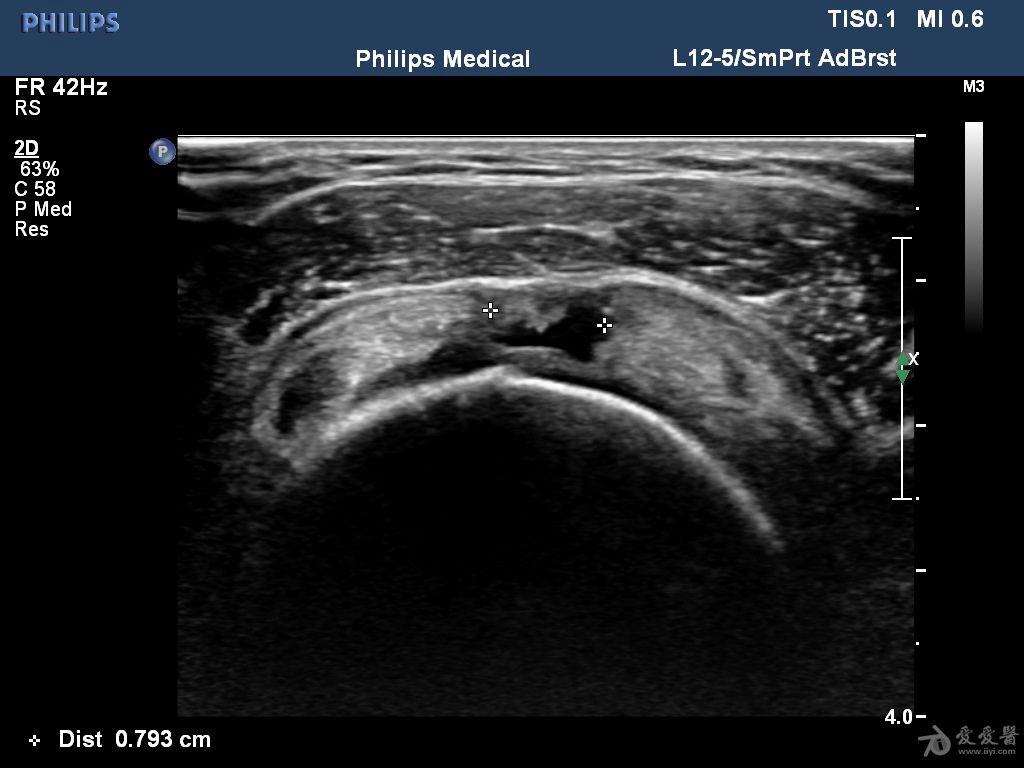

冈上肌腱腱体部分撕裂

肩关节mri常规扫描诊断部分撕裂不如全层撕裂那么准确,因此常需要进行